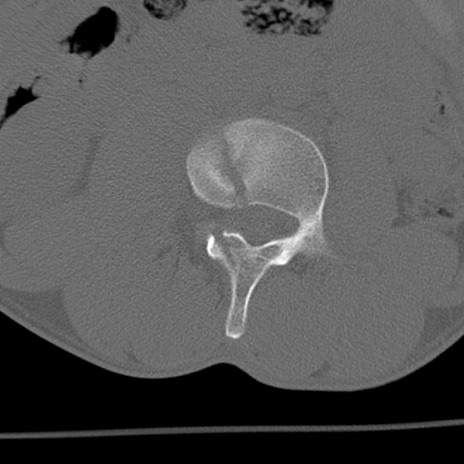

症例3 腰椎CT(横断像)

異常所見と診断は?

腰椎CT